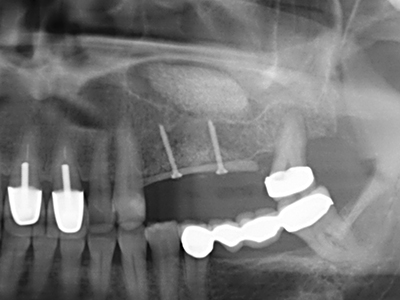

Пиезохирургията има допълнителни предимства при събиране на костни блокове. В допълнение към високата прецизност при остеотомията, описана по-горе, употребата на фините режещи накрайници значително намаляват загубата на материал. Голяма загуба на материал по време на събиране може да се очаква с дебелите накрайници, особено при употреба на борери Линдеман (Lakshmiganthan, Gokulanathan et al. 2012). Базалното разделяне, което е необходимо, особено за присадка на блок при ретромолар, е улеснено от специално създадени правоъгълни триони. В резултат на това, пиезохирургията е разглеждана като прецизна, улеснена и безопасна процедура за събиране на костни блокове в ретромоларното пространство (Happe 2007) (Фиг. 1-12).